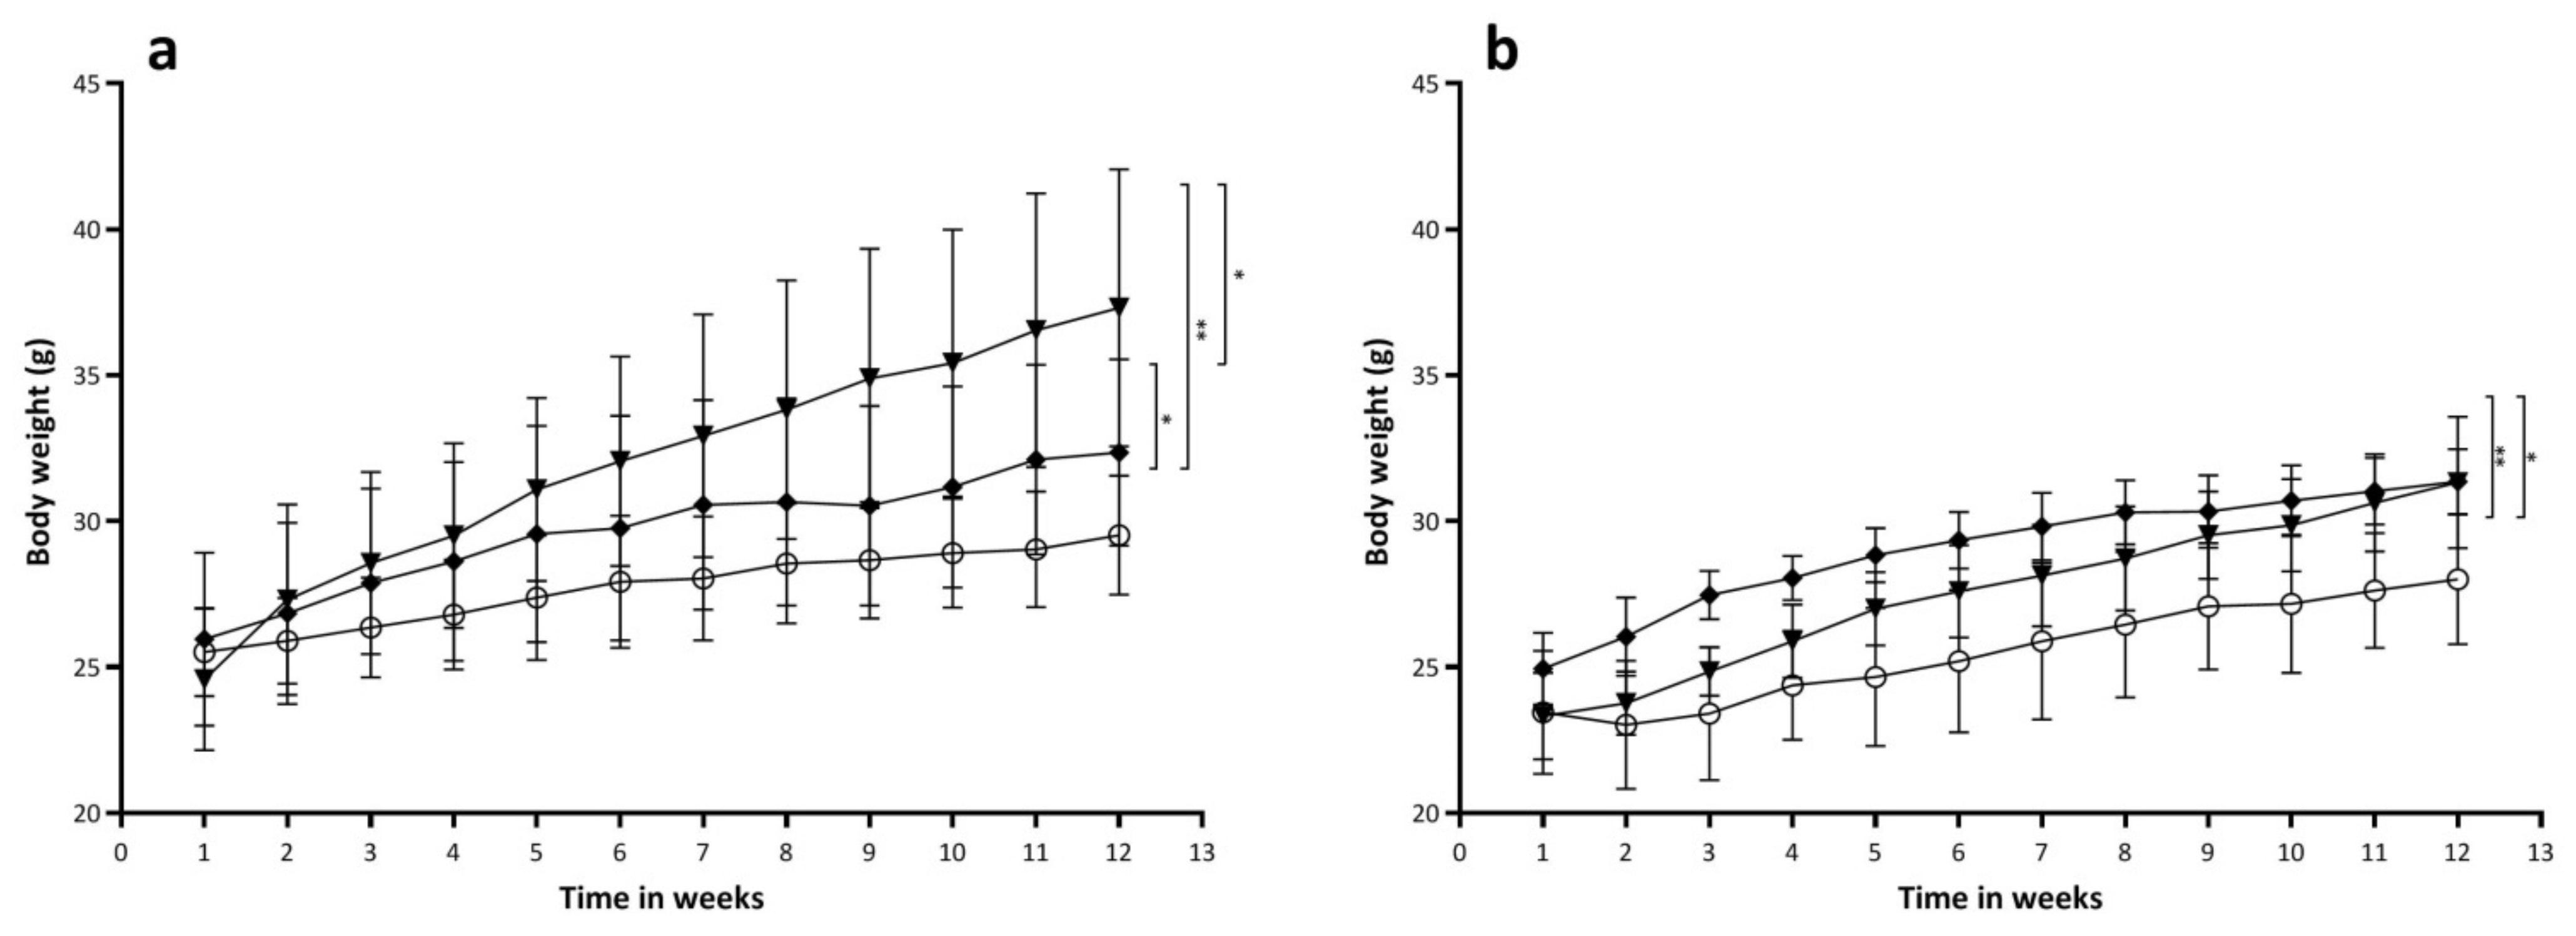

2.4. Effects of Diets on Body Weight and Body Composition